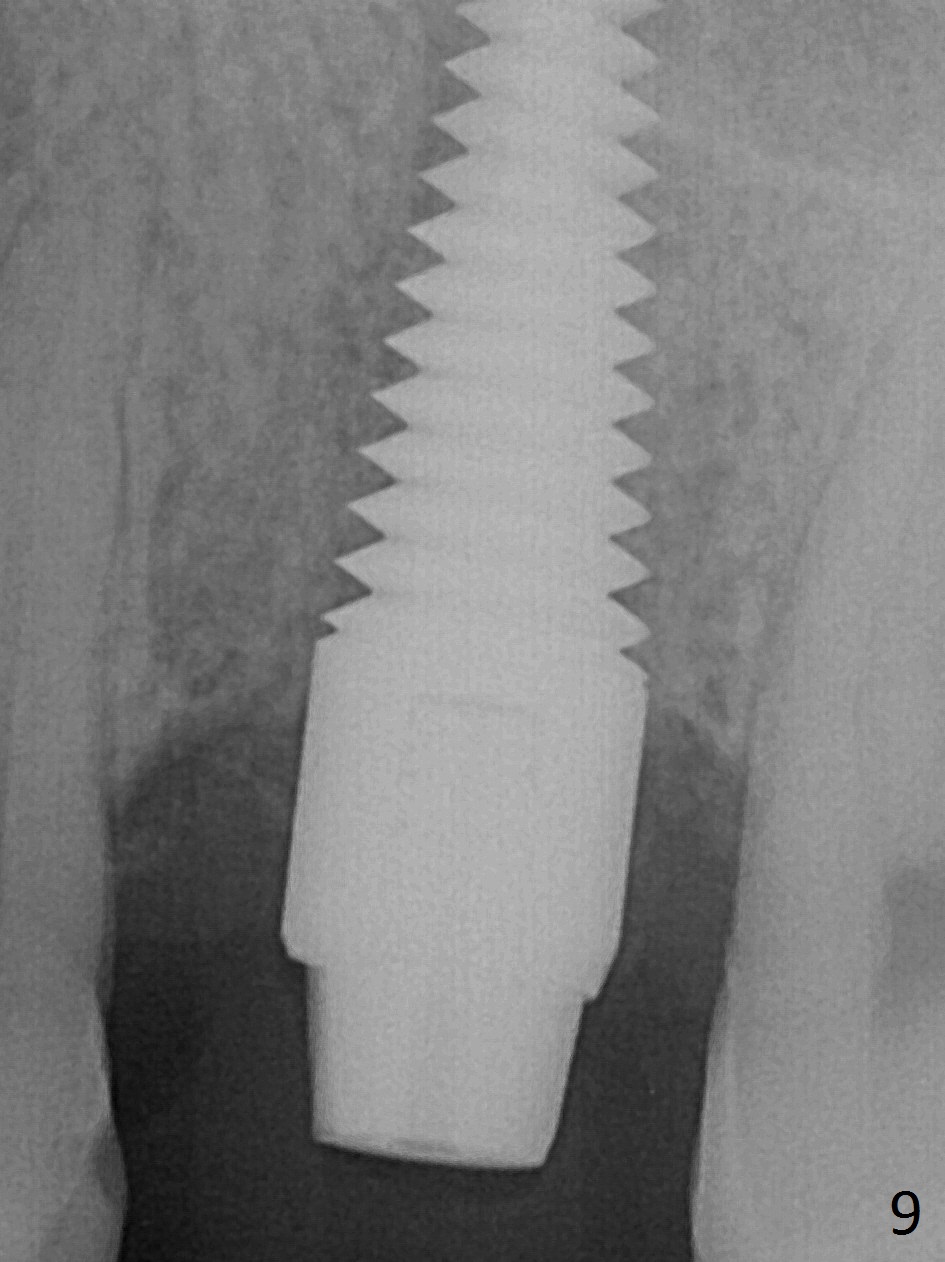

A much smaller implant should be used (e.g.4.5 mm) in order to save the septum. But the apical granulation tissue above the septum cannot be removed completely. There is no bone loss around the implant 4 months postop (Fig.9), although the gingiva is unhealthy because of lack of oral hygiene locally. The immediate provisional is not reseated with oral hygiene instruction. Impression will be taken in 2 weeks. Take photos to show disappearance of the fistula.